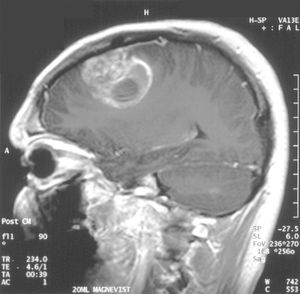

MRI로 볼 때, 교모세포종은 종종 환상 강화 병변으로 나타난다. 그러나 농양, 전이, 종괴성 다발성 경화증 등도 유사한 모습을 보일 수 있어 이 모습만으로는 특정할 수 없다.[61] CT 또는 MRI에서 교모세포종으로 의심되는 질환의 확진은 정위 생검 또는 종양 절제 및 병리적 확인을 위한 개두술이 필요하다. 종양 등급은 종양의 가장 악성인 부분에 기반하므로, 생검 또는 아전 절제술은 병변의 등급을 낮게 평가하는 결과를 초래할 수 있다.

; MRI

: T1 강조 영상에서는 종양이 약간 저신호역, T2 강조 영상에서는 종양과 그 주변의 뇌부종이 고신호역이 된다. 가돌리늄을 사용한 조영 MRI에서는 종양의 변연이 고신호역이 되는 한편, 종양 내부는 괴사 등을 반영하여 저~고신호역이 뒤섞인 영상이 되는 경우가 많다. 이 소견을 링 강화라고 칭한다. 또한, 링 강화는 교모세포종에 특이적인 소견이 아니며, 뇌농양, 전이성 뇌종양 등이 감별로서 거론되는 경우가 많다.

- MRI: T1 강조 영상에서는 종양이 약간 저신호역, T2 강조 영상에서는 종양과 그 주변의 뇌부종이 고신호역이 된다. 가돌리늄을 사용한 조영 MRI에서는 종양의 변연이 고신호역이 되는 한편, 종양 내부는 괴사 등을 반영하여 저~고신호역이 뒤섞인 영상이 되는 경우가 많다. 이 소견을 링 강화라고 칭한다. 또한, 링 강화는 교모세포종에 특이적인 소견이 아니며, 뇌농양, 전이성 뇌종양 등이 감별로서 거론되는 경우가 많다.

- MRI: T1 강조 영상에서는 종양이 약간 저신호역, T2 강조 영상에서는 종양과 그 주변의 뇌부종이 고신호역이 된다. 가돌리늄을 사용한 조영 MRI에서는 종양의 변연이 고신호역이 되는 한편, 종양 내부는 괴사 등을 반영하여 저~고신호역이 뒤섞인 영상이 되는 경우가 많다. 이 소견을 링 강화라고 칭한다. 링 강화는 교모세포종에 특이적인 소견이 아니며, 뇌농양, 전이성 뇌종양 등이 감별로서 거론되는 경우가 많다.